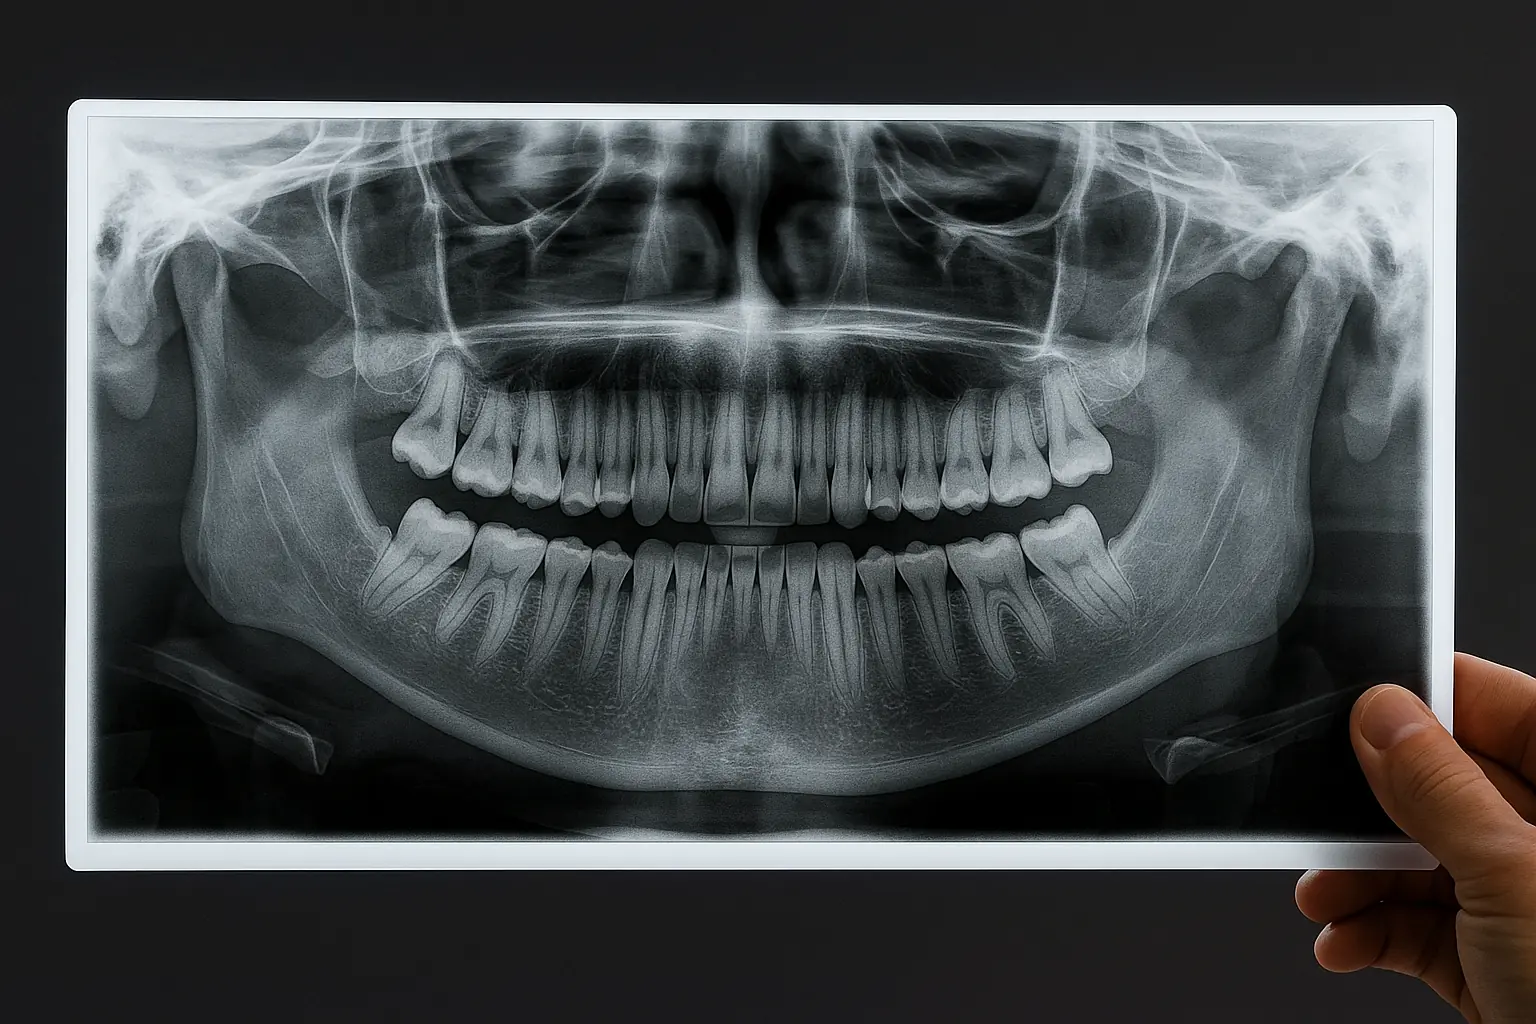

Un examen clínico y radiográfico completo puede identificar el origen exacto del problema y determinar el tratamiento más adecuado.